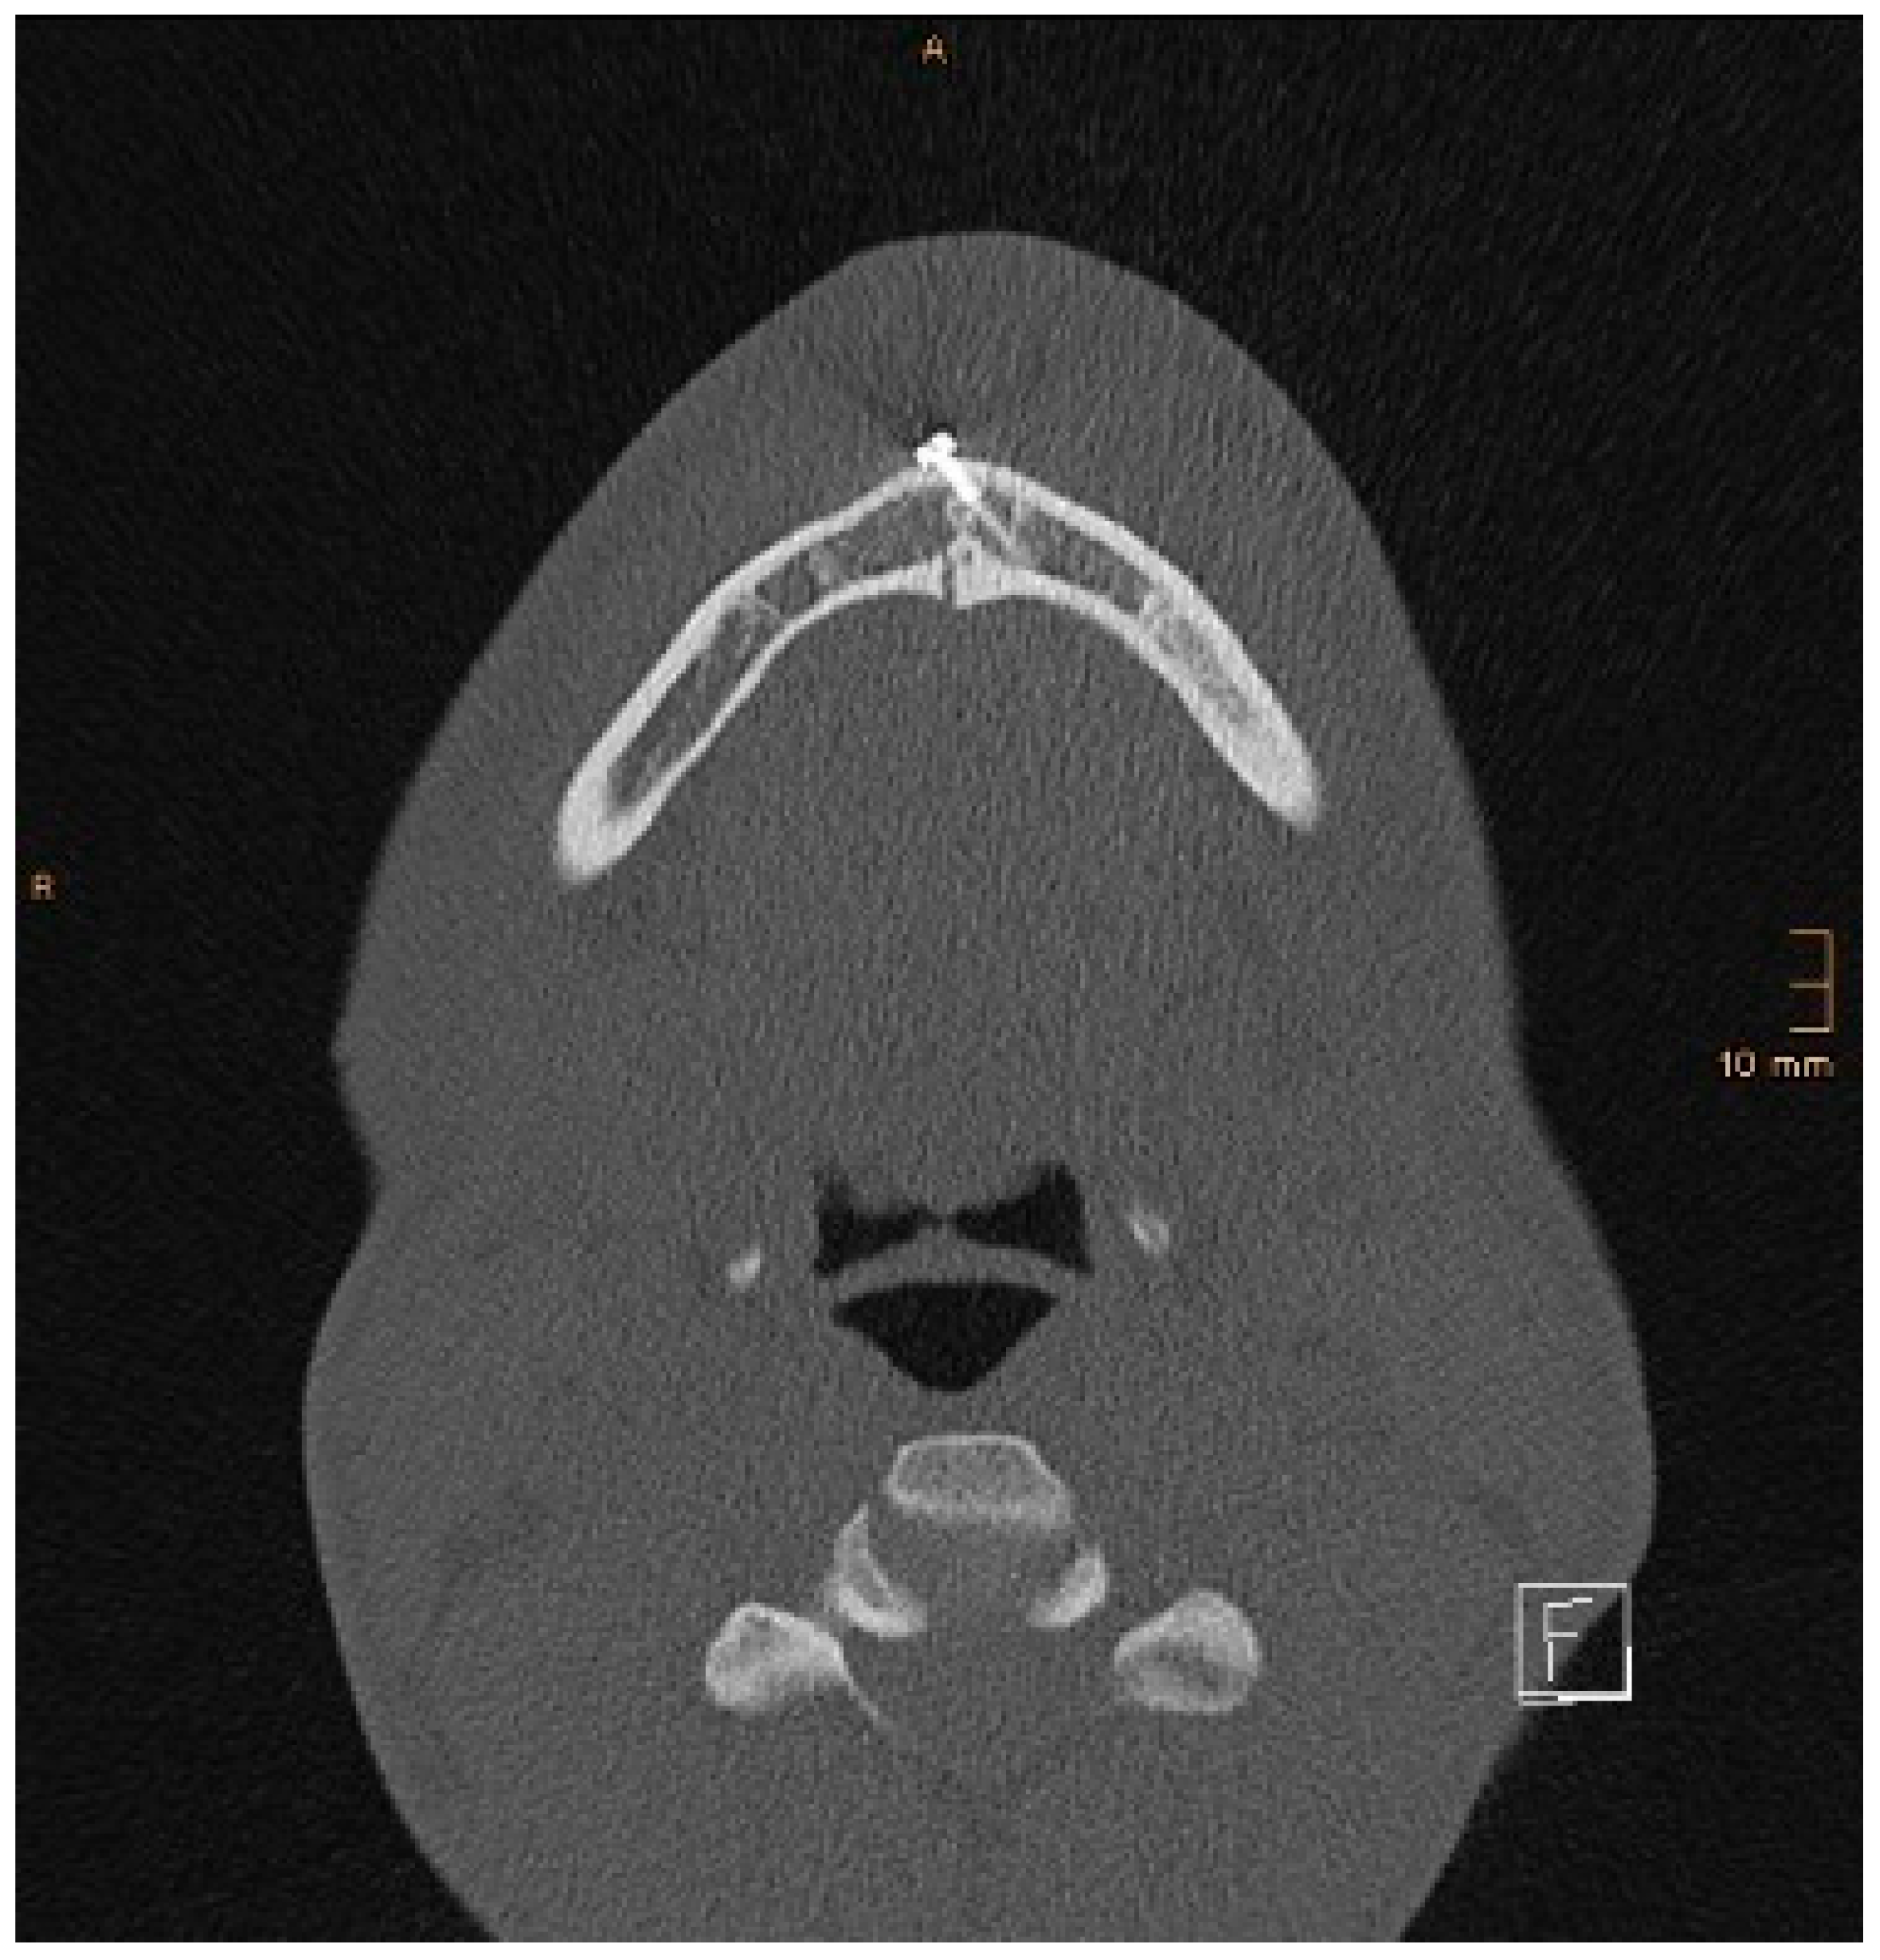

Two operations had to be redone because of inadequate reposition in the symphysis/parasymphysis with broad (>2 mm) lingual splay. In both cases, straight miniplates were removed. Osteosynthesis was achieved with lag screws. Figure 3 depicts plate osteosynthesis of a symphyseal fracture with a broad lingual gap (Figure 3). Figure 4 shows the same patient after redo operation and osteosynthesis of the same fracture with a lag-screw and a marked reduction in the lingual splaying (Figure 4). Figure 5 demonstrates the condylar reduction in the frontal plane in the same patient. Figure 6 and Figure 7 show the patient’s occlusion (Figure 5, Figure 6 and Figure 7). The third redo operation was due to nonunion and infection of an angular fracture with fracture of the two condylar plates. In this case, after removal of the infected miniplate, the angle fracture was stabilized with a reconstruction plate and a miniplate from an extraoral approach; the two broken miniplates at the condylar process were left in situ.

Figure 3. Axial CT scan with splaying of the lingual cortical bone in a symphyseal mandibular fracture after treatment with miniplates.